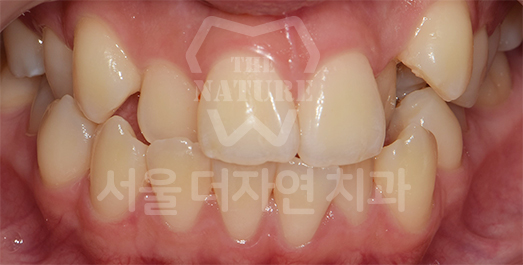

Facial Asymmetry Solution

If the cause is simply a dental occlusal discrepancy, conventional orthodontic treatment alone may be sufficient.

If the issue is muscular rather than skeletal,

treatment involves adjusting muscle volume.

In severe cases, treatment requires

mandibular osteotomy or orthognathic surgery.

BEFORE: 2012.10.12

AFTER: 2014.04.10